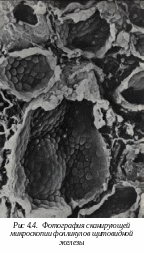

4.4. Микроскопическое строение щитовидной железы

Щ

итовидная железа состоит из двух долей, соединенных перешейком. Снаружи щитовидная железа покрыта двумя капсулами: первая служит продолжением перитрахиальной фасции (глубокой фасции шеи), вторая - истинная соединительно-тканная. Внутрь от капсулы отходят перегородки, образуя опорный аппарат железы, по которому в железу идут кровеносные сосуды и нервы. Так как перегородки не соединяются, паренхима железы не разделена до конца на дольки - железа имеет псевдодольчатое строение.

Т

ироциты формируют стенку фолликула и являются основной морфофункциональной единицей щитовидной железы. В железе около 30 млн. фолликулов, диаметром от 0,05 до 0,5 мм, окруженных базальной мембраной. Тироциты синтезируют тироксин и трийодтиронин. Образование гормонов тироцитов проходит ряд стадий.